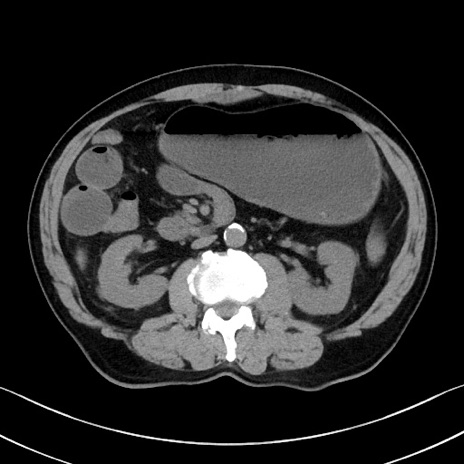

症例35(横断像)

【症例】70歳代 男性

【主訴】腹部膨満、嘔吐

【現病歴】昨日より腹部膨満感出現。本日増悪し、仙痛出現。嘔吐あり、受診。

【既往歴】糖尿病、胆摘後

【身体所見】BP 149/80mmHg、HR 74/min、BT 35.9℃、腹部:膨満、軟、圧痛なし。腸雑音減弱あり。上腹部正中切開瘢痕あり。

【データ】WBC 13500、CRP 1.72